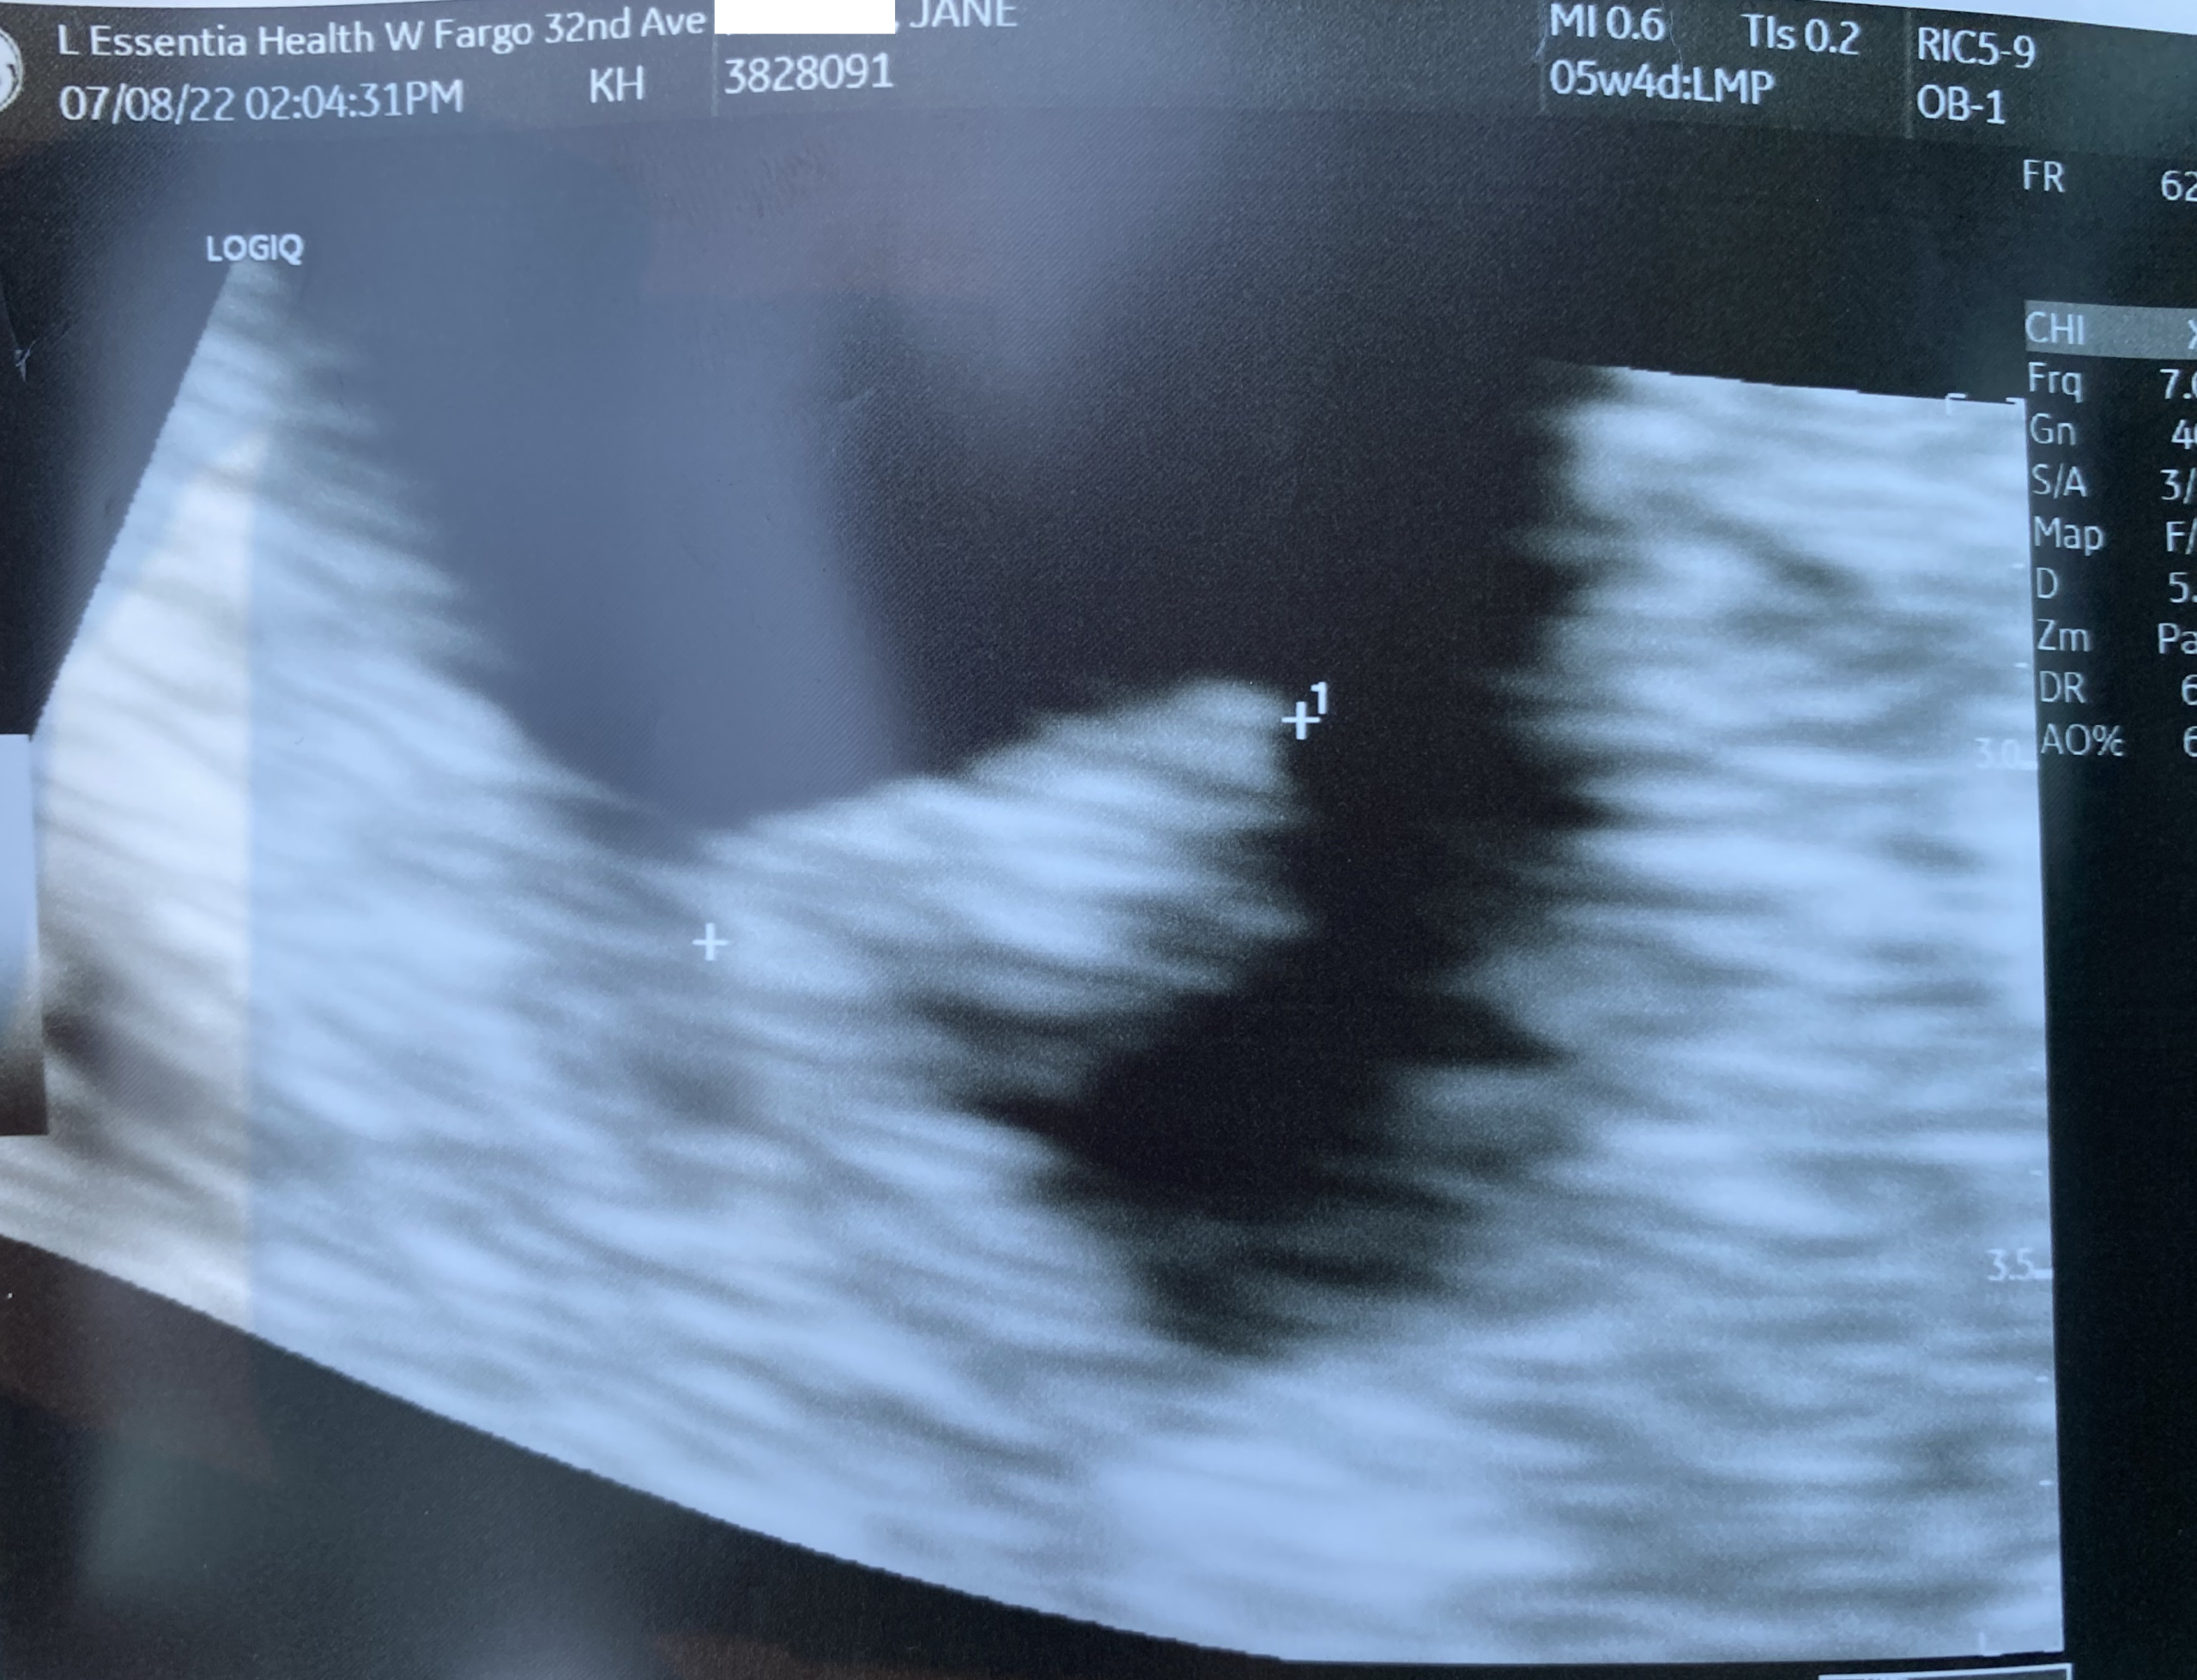

Our First Ultrasound 🥰

We just returned home from our first ultrasound, and everything couldn’t have been more perfect!! We drove up to Fargo this morning to meet up with Jane for lunch and then proceeded over to the

Read More »

July 8, 2022